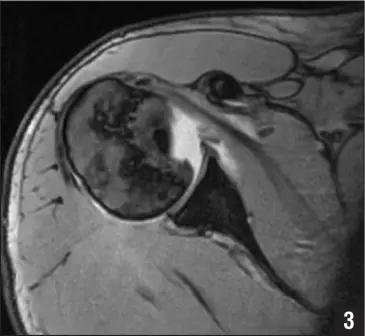

Hill-Sachs 损伤的 X 片(来源:Hill-Sachs Injuries of the Shoulder)

Hill-Sachs 损伤的 MR 片(来源:Hill-Sachs Injuries of the Shoulder)

Hill-Sachs 损伤的 CT 片 (来源:Hill-Sachs Injuries of the Shoulder)